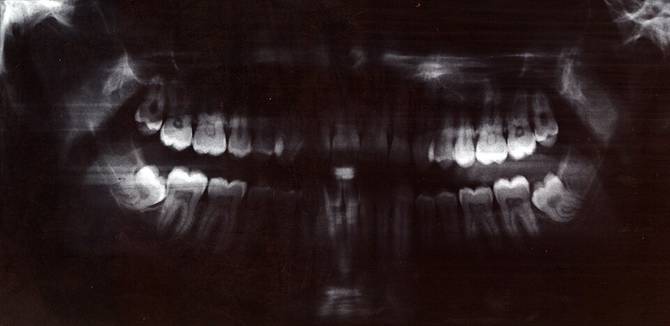

Les explosions de dents

Au 19e siècle, on a rapporté plusieurs cas d’explosions de dents, notamment en Pennsylvanie où un dentiste avait rencontré 3 cas semblables durant sa carrière. Ses patients lui avaient expliqué avoir entendu un gros bruit dans leur bouche provoqué par une explosion de leur propre dent. Il y a eu d’autres cas du même genre dans tout le pays, puis plus rien à partir du 20e siècle. Là, vous vous demandez ce qui a pu se passer, et vous avez bien raison d’être curieux, alors voici la réponse la plus probable : on soupçonne les plombages de l’époque composés d’un alliage de plomb, d’argent et d’étain. Les trois métaux combinés créaient une cellule électrochimique dans la dent qui pouvait exploser quand la personne s’allumait une petite clope. On a depuis (heureusement) arrêté de poser ce genre de plombages pour éviter de tous finir avec la mâchoire dégommée. C’est bien le progrès.